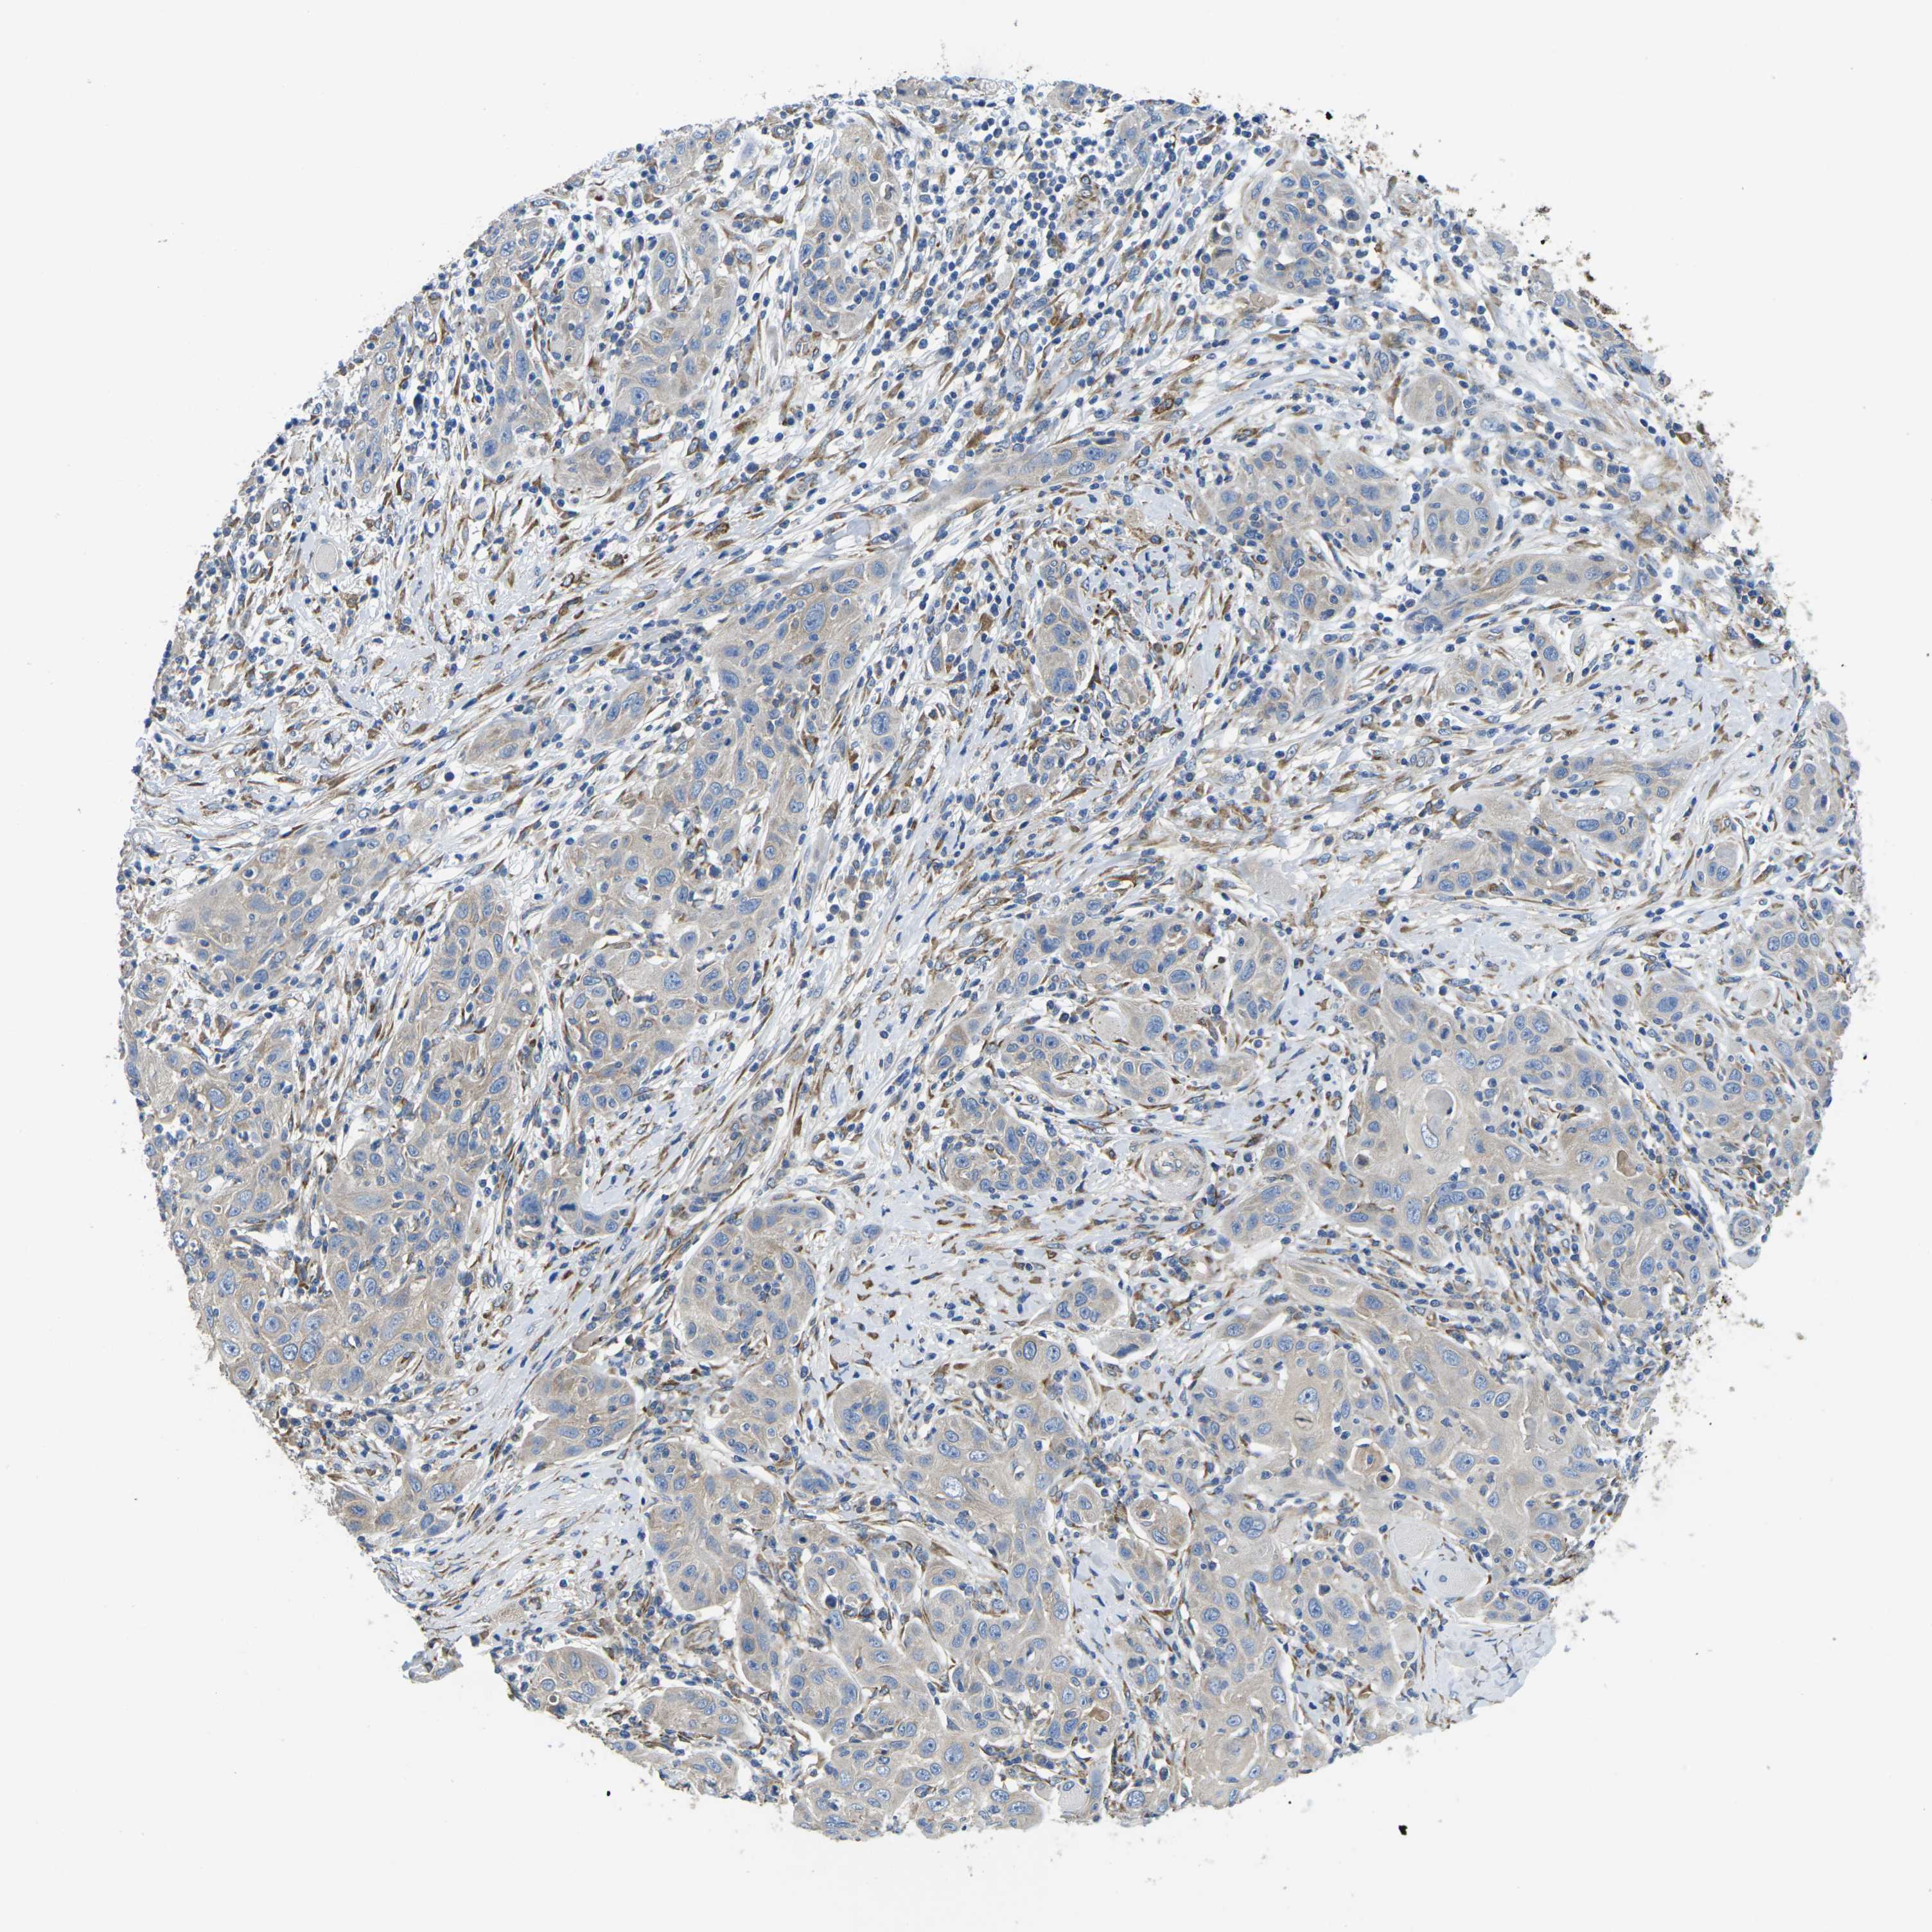

SKIN CANCER - Protein expressioni

A mouse-over function shows sample information and annotation data. Click on an image to view it in a full screen mode. Samples can be filtered based on level of antibody staining by selecting one or several of the following categories: high, medium, low and not detected. The assay and annotation is described here.

Antibody stainingi

Antibody staining in the annotated cell types in the current human tissue is reported as not detected, low, medium, or high, based on conventional immunohistochemistry profiling in selected tissues. This score is based on the combination of the staining intensity and fraction of stained cells.

Each image is clickable and will lead to virtual microscopy that enables deeper exploration of all samples and also displays staining intensity scores, fraction scores and subcellular localization as well as patient and tissue information for each sample.

Antibody HPA015716

Staining

High

Medium

Low

Not detected

Intensity

Strong

Moderate

Weak

Negative

Quantity

>75%

75%-25%

<25%

None

Location

Nuclear

Cytoplasmic/membranous

Cytoplasmic/membranous,nuclear

Squamous cell carcinoma in situ, NOS

Squamous cell carcinoma, NOS

Squamous cell carcinoma, metastatic, NOS

Basal cell carcinoma

Adnexal tumor, benign